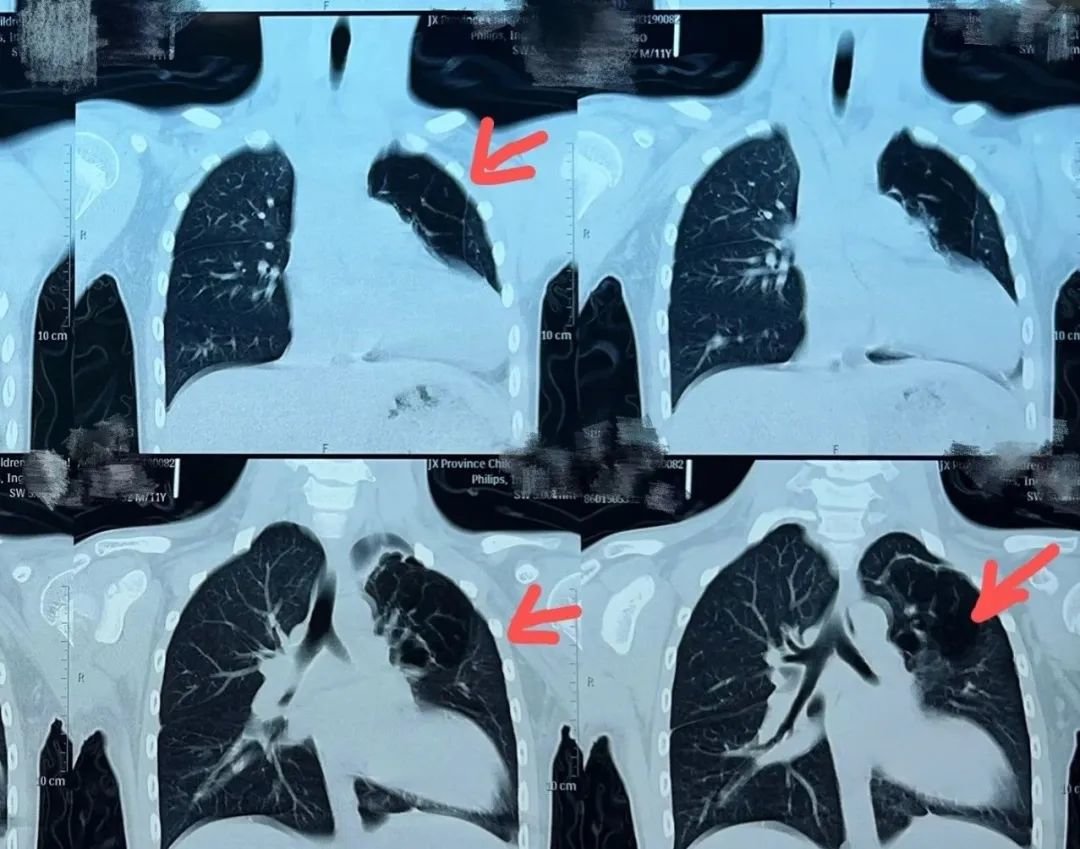

小东(化名)因为咳嗽咳痰、痰中带血、高热在当地多家医院就诊,效果不佳仍反复发作,于是来到江西省儿童医院心胸外科门诊,经过详细的检查发现罪魁祸首是左上肺的多个肺囊泡,肺囊泡导致小东反复的肺炎。

“小东反复咳嗽咳痰,痰中带血,感染重,已经出现胸痛症状,而且检查评估发现胸腔内组织粘连、心脏心包及纵隔胸膜缺失,心脏完全裸露在胸腔内,病变组织与心脏相邻,在狭小的空间内,手术操作难度较大,但是这个手术必须做,否则囊泡会导致肺部反复炎症使肺功能进一步受损。”心胸外科主任医师涂洪强在病情分析时说。